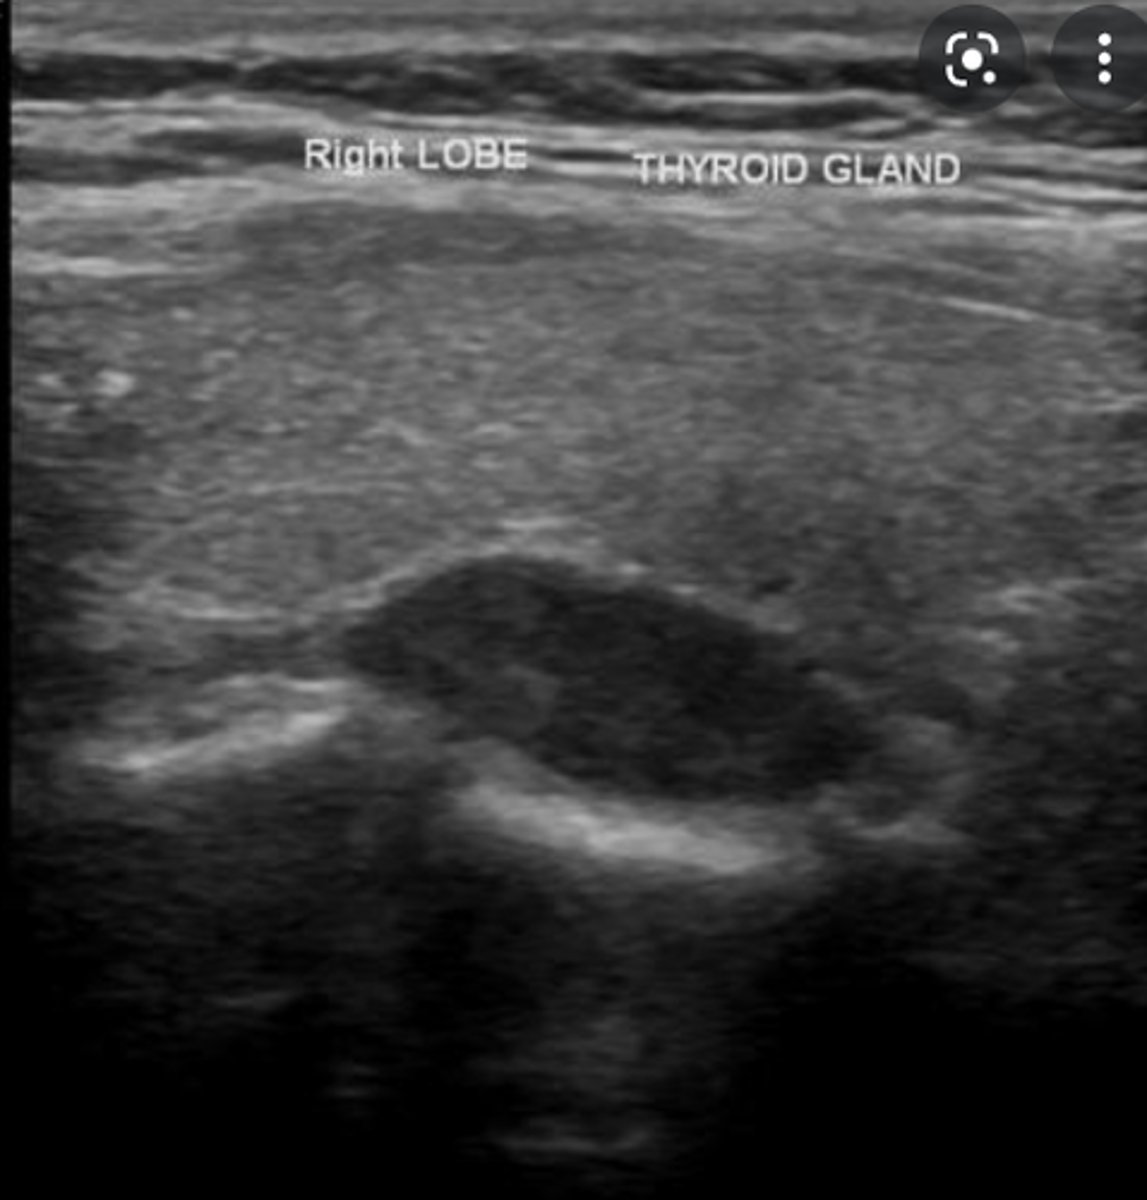

Sonographic Appearance:

-Thyroid lobes and isthmus appear as ____geneous solid structures demonstrating a medium-gray echo pattern with a surrounding thin ____echoic line

-Sternocleidomastoid muscle are _____ and oval in shape appearing ____echoic compared with the normal thyroid gland

-Strap muscles are _____ and ____echoic compared with the normal thyroid gland

-Longus colli muscles appear ____echoic compared with the normal thyroid gland

-Thyroid lobes and isthmus appear as homogeneous solid structures demonstrating a medium-gray echo pattern with a surrounding thin hyperechoic line

-Sternocleidomastoid muscle are large and oval in shape appearing hypoechoic compared with the normal thyroid gland

-Strap muscles are thin and hypoechoic compared with the normal thyroid gland

-Longus colli muscles appear hypoechoic compared with the normal thyroid gland